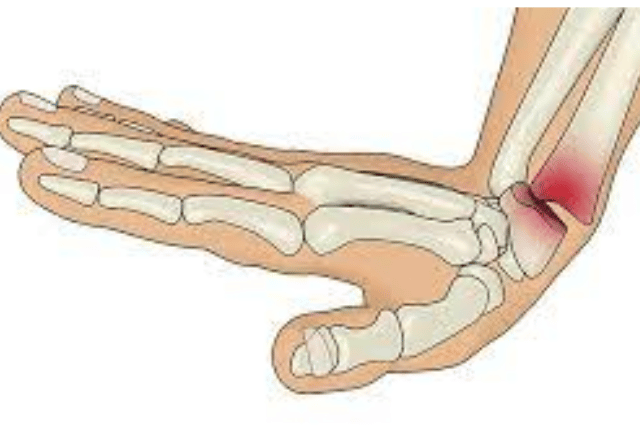

Fractures can be painful and require immediate attention. Our fracture clinic at Medilife Superspeciality Clinic Punawale is equipped with the latest technology and equipment to provide accurate diagnosis and effective treatment for fractures. Our team of orthopaedic specialists ensures that you receive the best possible care and treatment for your fracture, whether it requires casting, splinting, or surgery.